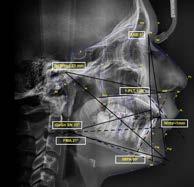

En la radiografía lateral de cráneo ( Figura 6 ) se ve la línea estética de Rickets, que el labio superior se encuentra a +0.5 mm y el inferior a -2 mm. En las mediciones cefalométricas más importantes en la figura 11 un ANB de 5º, GoGn-SN de 33º y FMA de 21º crecimiento normodivergente y Witts de -1 mm. A los criterios dentales encontramos

1-PLT de 129º e IMPA 99º proinclinación de incisivos tanto superiores como inferiores. En la radiografía panorámica (Figura 7), la presencia de 32 órganos dentarios, con terceros molares inferiores aún sin erupcionar y terceros molares superiores

Figura 6. Rx. cráneo lateral inicio progreso con trazos.

Secuencia de radiografías laterales de cráneo (Figura 15) vemos que el ANB disminuyo 1º de inicio a fin clase I con tendencia a clase II esquelética a final. Reducción de Witts 0.5 mm final, crecimiento normodivergente. Mandíbula más pequeña que el maxilar, cambio por el avance mandibular.